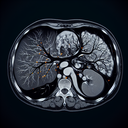

МРТ печінки

Магнітно-резонансна томографія (МРТ) печінки — це візуалізаційна процедура, яка дозволяє отримати детальні зображення цього органу та навколишніх структур. Це допомагає діагностувати різні захворювання. ### **Підготовка до МРТ печінки:** 1...